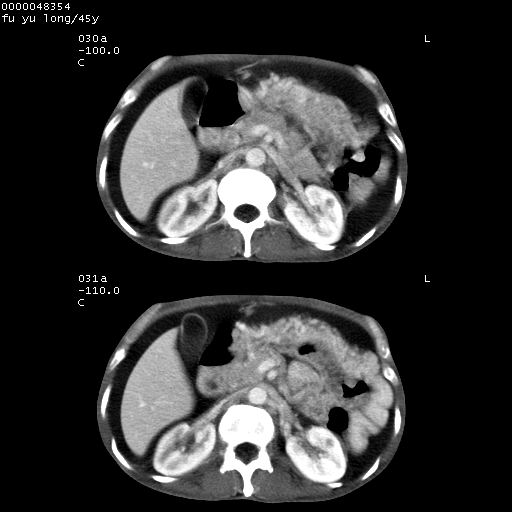

以下是引用lkc8963在2008-5-30 8:44:00的发言:[br]胃窦癌伴网膜(胃结肠韧带)/腹膜及腹膜后淋巴结转移.

以下是引用医影拾贝在2008-5-30 2:38:00的发言:[br]气肿性胃炎、胃十二指肠溃疡、腹膜炎,考虑穿孔可能性较大